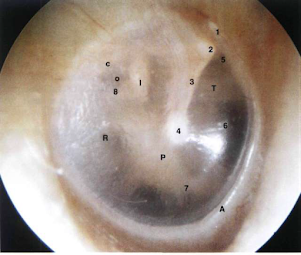

Oido derecho. timpánico normal

1 = parte fláccida; 2 = corto proceso del martillo; 3 = mango del martillo; 4 = umbo; 5 =receso supratubárico; 6 = orificio tubárico;7=células aéreas hipotimpánicas; 8 = tendón estapedio; c = cuerda del tímpano; I = yunque; P = promontorio; o = ventana ovalada; R = ventana redonda; T = tensor del tímpano; A = anillo.

Oido derecho. División de la membrana timpánica.

en cuatro cuadrantes:

A.S. = anterosuperior; AI. = anteroinferior; PS = posterosuperior; PI. = posteroinferior. Esta división Facilita la descripción de diferentes afecciones patológicas de la membrana timpánica.